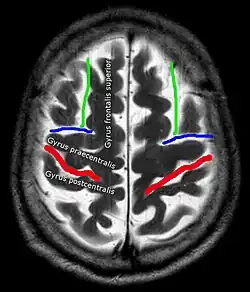

In der Computertomographie und Magnetresonanztomographie ist für die korrekte Lokalisation eines Befundes eine sichere Identifikation des Sulcus centralis oft einer der ersten Schritte. Hierfür haben sich in Abhängigkeit von der Schnittebene verschiedene Strategien etabliert.[4] Beispiele:

Axial Sagittal

1. Lateral vom Interhemisphärenspalt: Gyrus frontalis superior

2. Lateral davon: Sulcus frontalis superior (grün)

3. Dieser trifft dorsal auf den Sulcus praecentralis (blau)

4. Dorsal davon Gyrus praecentralis

5. Dorsal davon Sulcus centralis (rot)